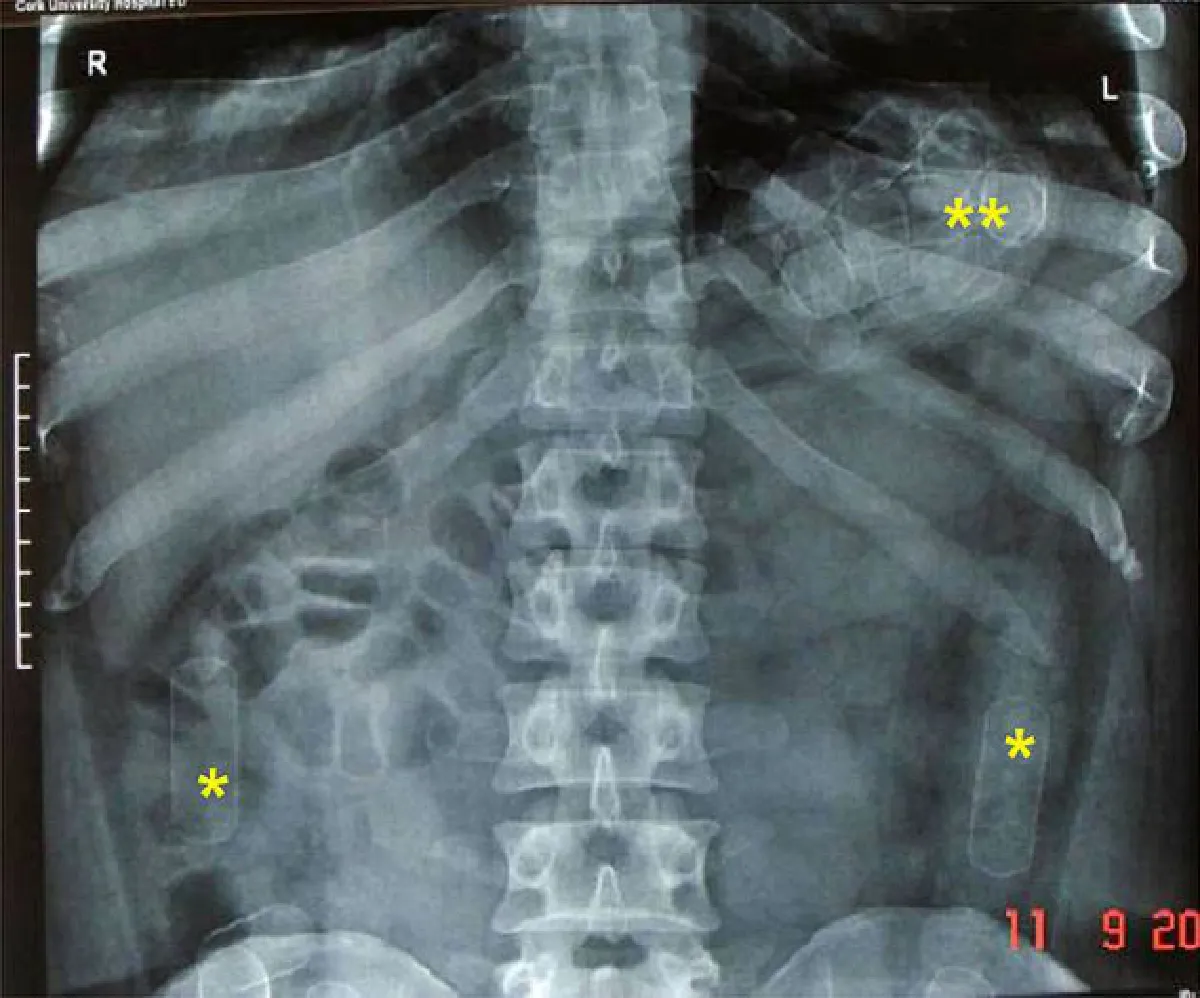

Photo above is an X-ray showing packages that a drug mule swallowed to hide illegal drugs they were smuggling (Source: Wikipedia)